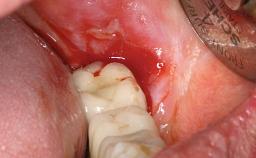

The fracture of an implant after it has been restored is one of the most severe complications. It most frequently occurs in partially edentulous jaws (1.5%). Most implant fractures involve implants with a diameter of 3.75 mm made of commercially pure titanium (Eckert 2010). Unfortunately, many cases are not reported or documented by the clinicians involved in resolving the problems created by the fracture. This case report describes the management of an implant fracture at site 36 in a middle-aged male patient. The implant had been restored with a screw-retained metal-ceramic crown.